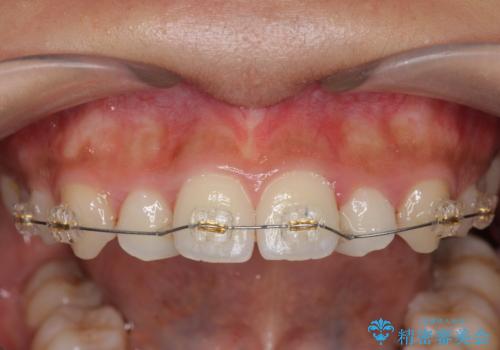

- 前歯のガタつき、上下たがい違いになっている歯並び(クロスバイト)の改善を求めて来院されました。

インビザラインによる矯正治療を行いますが、クロスバイトの改善をワイヤー部分矯正で事前に行うことにより治療期間の短縮する治療計画を立案します。

上下すれ違った噛み合わせはマウスピースでは改善に時間がかかり、またねじれが残ってしまうことも多々見られます。

マウスピース矯正を行う前に、これらの症状の改善の得意なワイヤー部分矯正を行うことで治療期間を短縮し、確実にすれ違いを改善することができます。